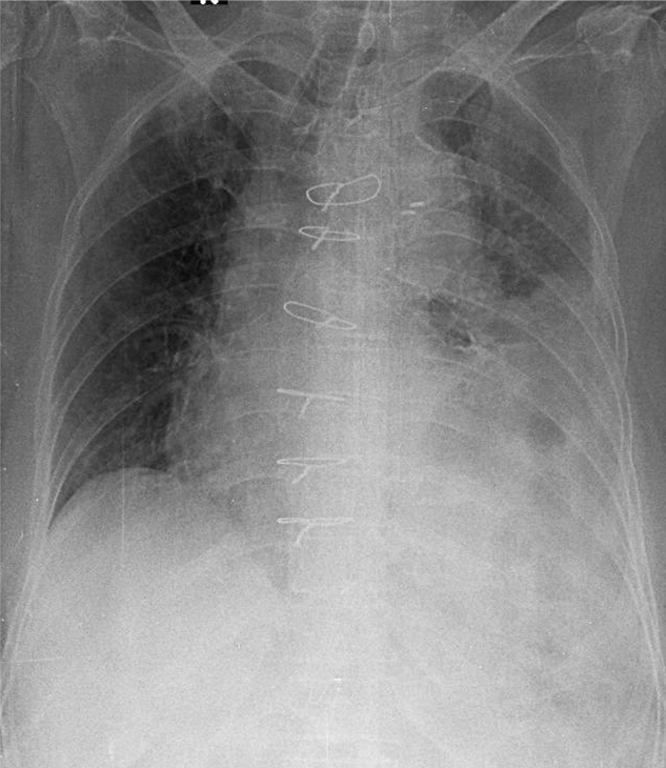

1-Khí phế quản lệch (P) kèm đóng vôi 2-Viêm thùy dưới phổi (T) 3-Tràn dịch màng phổi (T) 4-Cung động mạch chủ dãn kèm đóng vôi 5-Chỉ kim loại thành ngực dọc xương ức